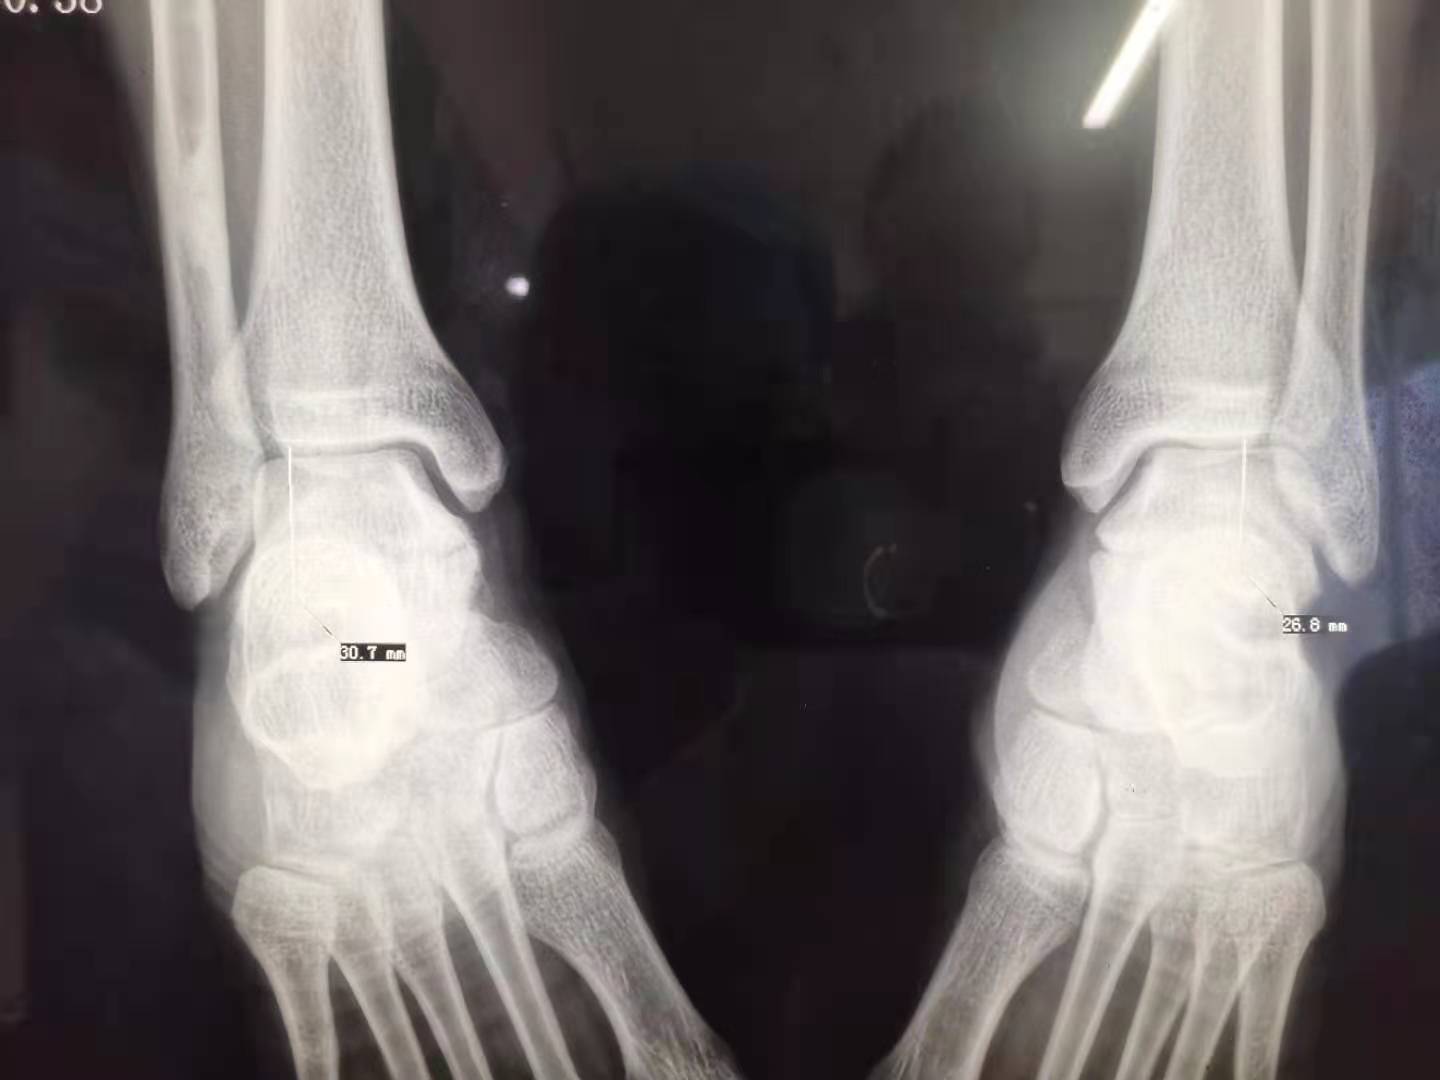

那么这种腓骨的移位就与我足部的劳损,足内翻时局部的韧带肌肉牵拉腓骨下移位有直接的关系了。为研究足部的骨关节位置关系,特意做了一双足踝的照片以协助诊断,测量关节间隙到腓骨下端的距离表明右腓骨下移位了,见下图。